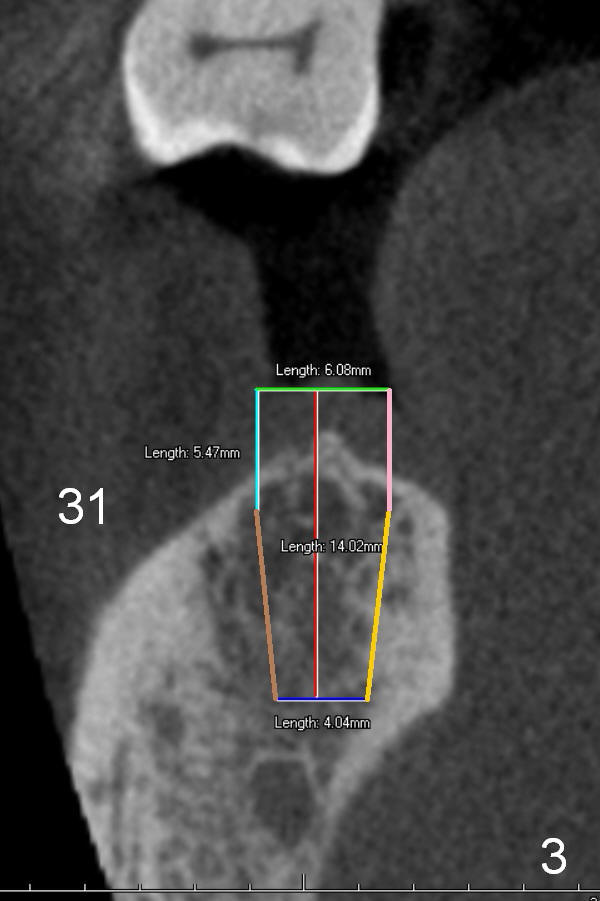

A 74-year-old man has lost the teeth #30 and 31 for a while. He is wearing a RPD and is not comfortable with it. CT analysis reveals that 5x14 and 6x14 mm implants could be placed at the site of #30 and 31, respectively (Fig.1 CT sagittal section), Fig.2,3 (coronal sections)). If implant threads are exposed, decorticate locally, place bone graft (Fig.2 red circle) and a piece of extended use collagen membrane (circling the implant, to be sutured first). If insertion torque is high for both implants, splint provisionals and minimal occlusal contact. For the best positioning, take Alginate impression when the patient returns for #8,9 implant placement.